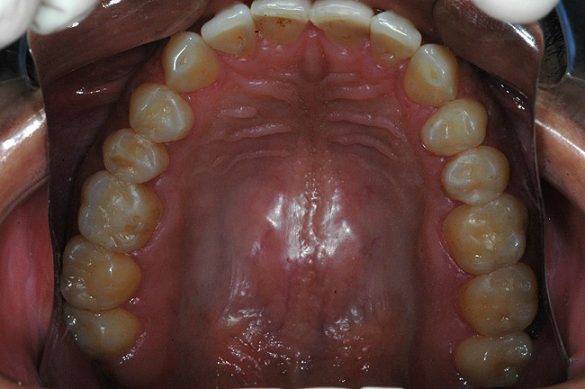

În cursul examinării clinice s-a notat o igienă orală satisfăcătoare. Pacientul prezenta coroziunea suprafeţelor ocluzale şi orale la dinţi maxilari şi mandibulari posteriori (fig. 1). Avea, de asemenea, arii expuse de ţesut dentinar (fig. 3) şi restaurări din amalgam compromise în lipsa sprijinului adecvat.